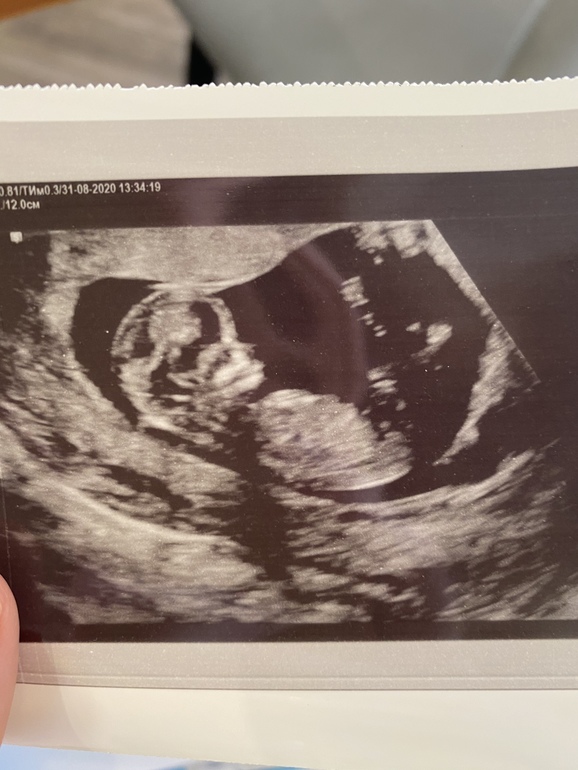

Первый скрининг❤️11 недель

Сходили мы на первый скрининг ровно в 11 недель. Умудрилась на ранних сроках переболеть орз, лечили антибиотиками, поэтому очень боялась за малыша.. Еще где-то прочитала, что бывает, что у детишек нет носа (хоспади, откуда я это вычитала😂), поэтому еще очень переживала за нос🤪😃

Так вот, мы опережаем на недельку)

Ктр 57 мм

Чсс 157 уд/мин

Носовая кость визуализируется😃

Толщ. воротн. пр 1,6мм

Заключение: беременность 12 недель !! И 2 дня

Предположили девочку)) почему, не пойму)

Еще смешно было, что дитенок спал, будили его 4 раза, чтоб нормально измерить. Хоть делала бесплатно по направлению от ЖК, все были очень вежливые и никуда меня не торопили.. даже удивилась))

Кто разбирается в узи, на кого дитенок похож? Мальчик, девочка?))🤰